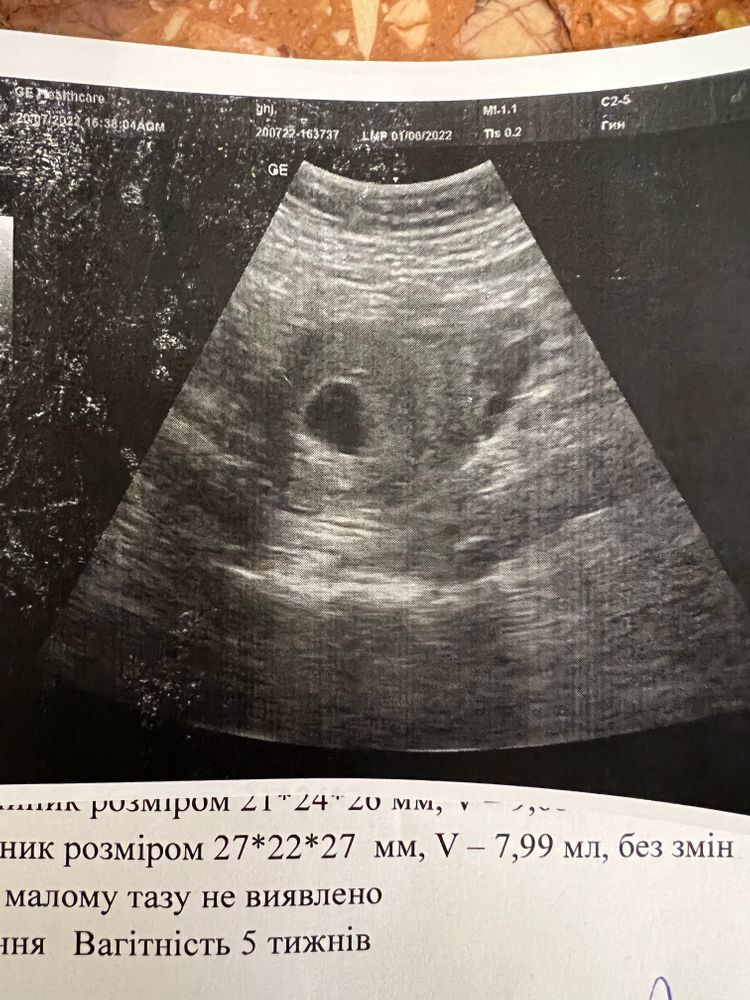

Сегодня была на узи, по месячным должно быть 7 недель. На узи нашли только плодное яйцо 24 мм которое соответствует 5 недель. Я просто разбита, ведь в 7 недель уже должен быть и эмбрион и должно быть сердцебиение. Плачу..

20.07.2022